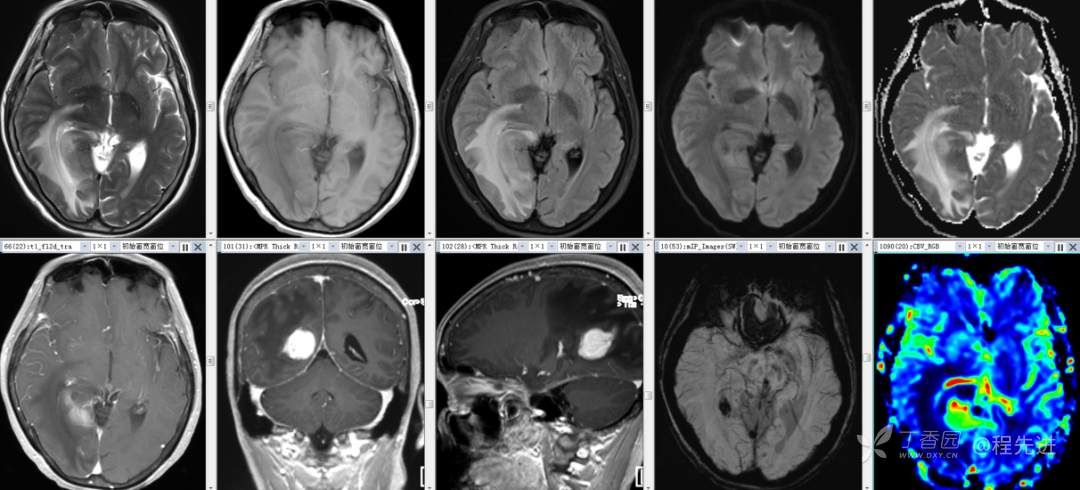

辅助检查:外院头颅 CT 示:右侧顶枕叶占位。

颅脑 MRI 平扫+增强: